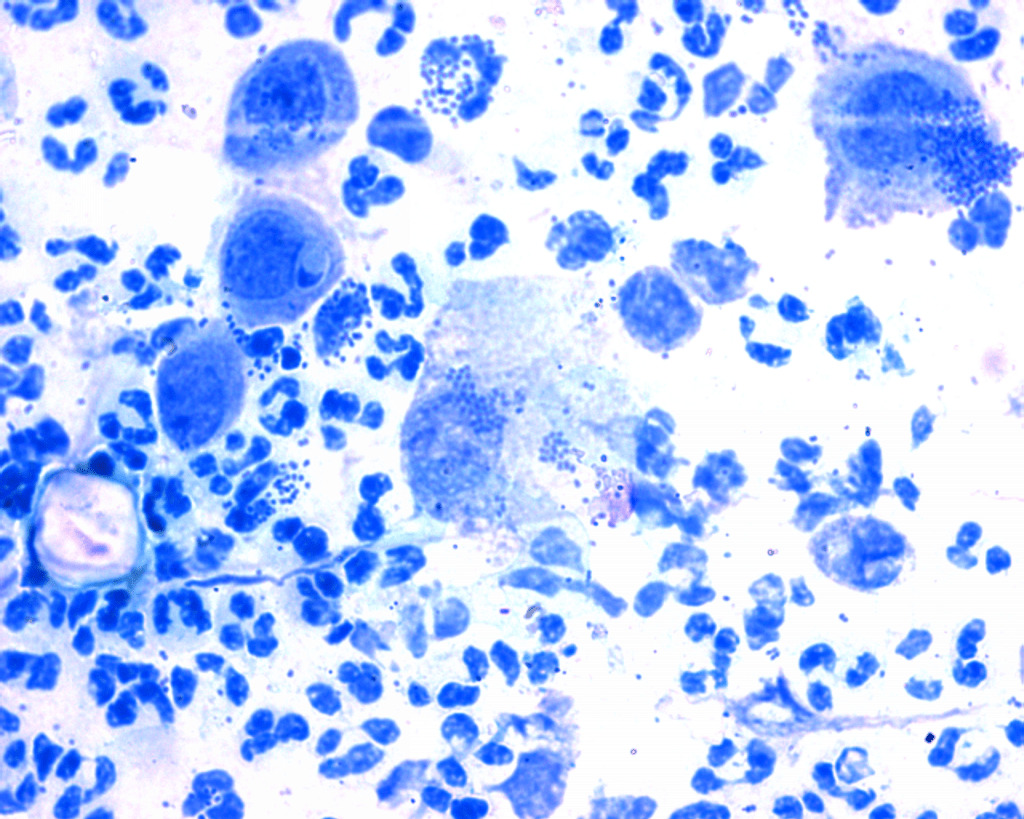

- Бактериоскопия. Материалом для исследования является мазок со слизистой оболочки влагалища и шейки матки. Его наносят на специальное стекло и изучают в лаборатории при помощи метода окрашивания. Лаборант выделяет число бактерий конкретного типа и отражает результаты в бланке ответов.